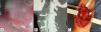

A 39-year-old man had a past medical history of appendectomy due to complicated appendicitis, as well as numerous symptoms of lower gastrointestinal bleeding from probable hemorrhoidal disease that were untreated. He was admitted to the hospital for 2-day progression of symptoms characterized by melena and hematemesis. Endoscopy was performed that identified: pulsatile, erythematous, and congestive polypoid tumoral lesion, 3 x 4cm in diameter, in the right posterolateral wall of the hypopharynx. There were no signs of active bleeding (fig. 1A), but fibrin-covered ulcers extended from the soft palate and proximal portion of the right piriform sinus. Twenty-four hours later, the patient presented with a new episode of bleeding. Angiotomography revealed a thickened hypopharynx and an irregular, right hypodense image, 21 x 17 x 17mm in diameter, at the level of the inferior constrictor muscle that protruded toward the lumen, obstructing 50% of it, with contrast medium leakage. A saccular image dependent on the aberrant artery was also observed that emerged from the trunk of the superior thyroid artery as a probable variant of the lingual artery (fig. 1B). After angiotomography, the patient presented with sudden onset of massive bleeding through the oral cavity. He became hemodynamically unstable, with AP of 48/30mmHg and MAP of 33mmHg. Carotid arteriography was performed (fig. 2A) that identified a 1.5-mm vessel at the level of the bifurcation that drains into the trachea above and to the right of the vallecula. Two sacs measuring approximately 5 and 8mm were observed along its tract. Failed embolization resulted in carrying out vascular examination of the neck with selective ligation of the first branch of the right external carotid artery (thyrolingual trunk) (fig. 1C). Bleeding control was adequate, and the patient was sent to the intensive care unit, where he underwent blood transfusion. His postoperative period was uneventful.

A) Arteriography. Yellow arrow: internal carotid artery; dotted yellow arrow: external carotid artery; purple arrow: facial artery; green arrow: lingual artery; blue arrow: aneurysm of the lingual artery; white arrow: thyrolingual trunk; dotted white arrow: superior thyroid artery. B) Most frequent anatomy of the branches of the external carotid artery. C) Thyrolingual trunk, seen in 0.99% of cases.